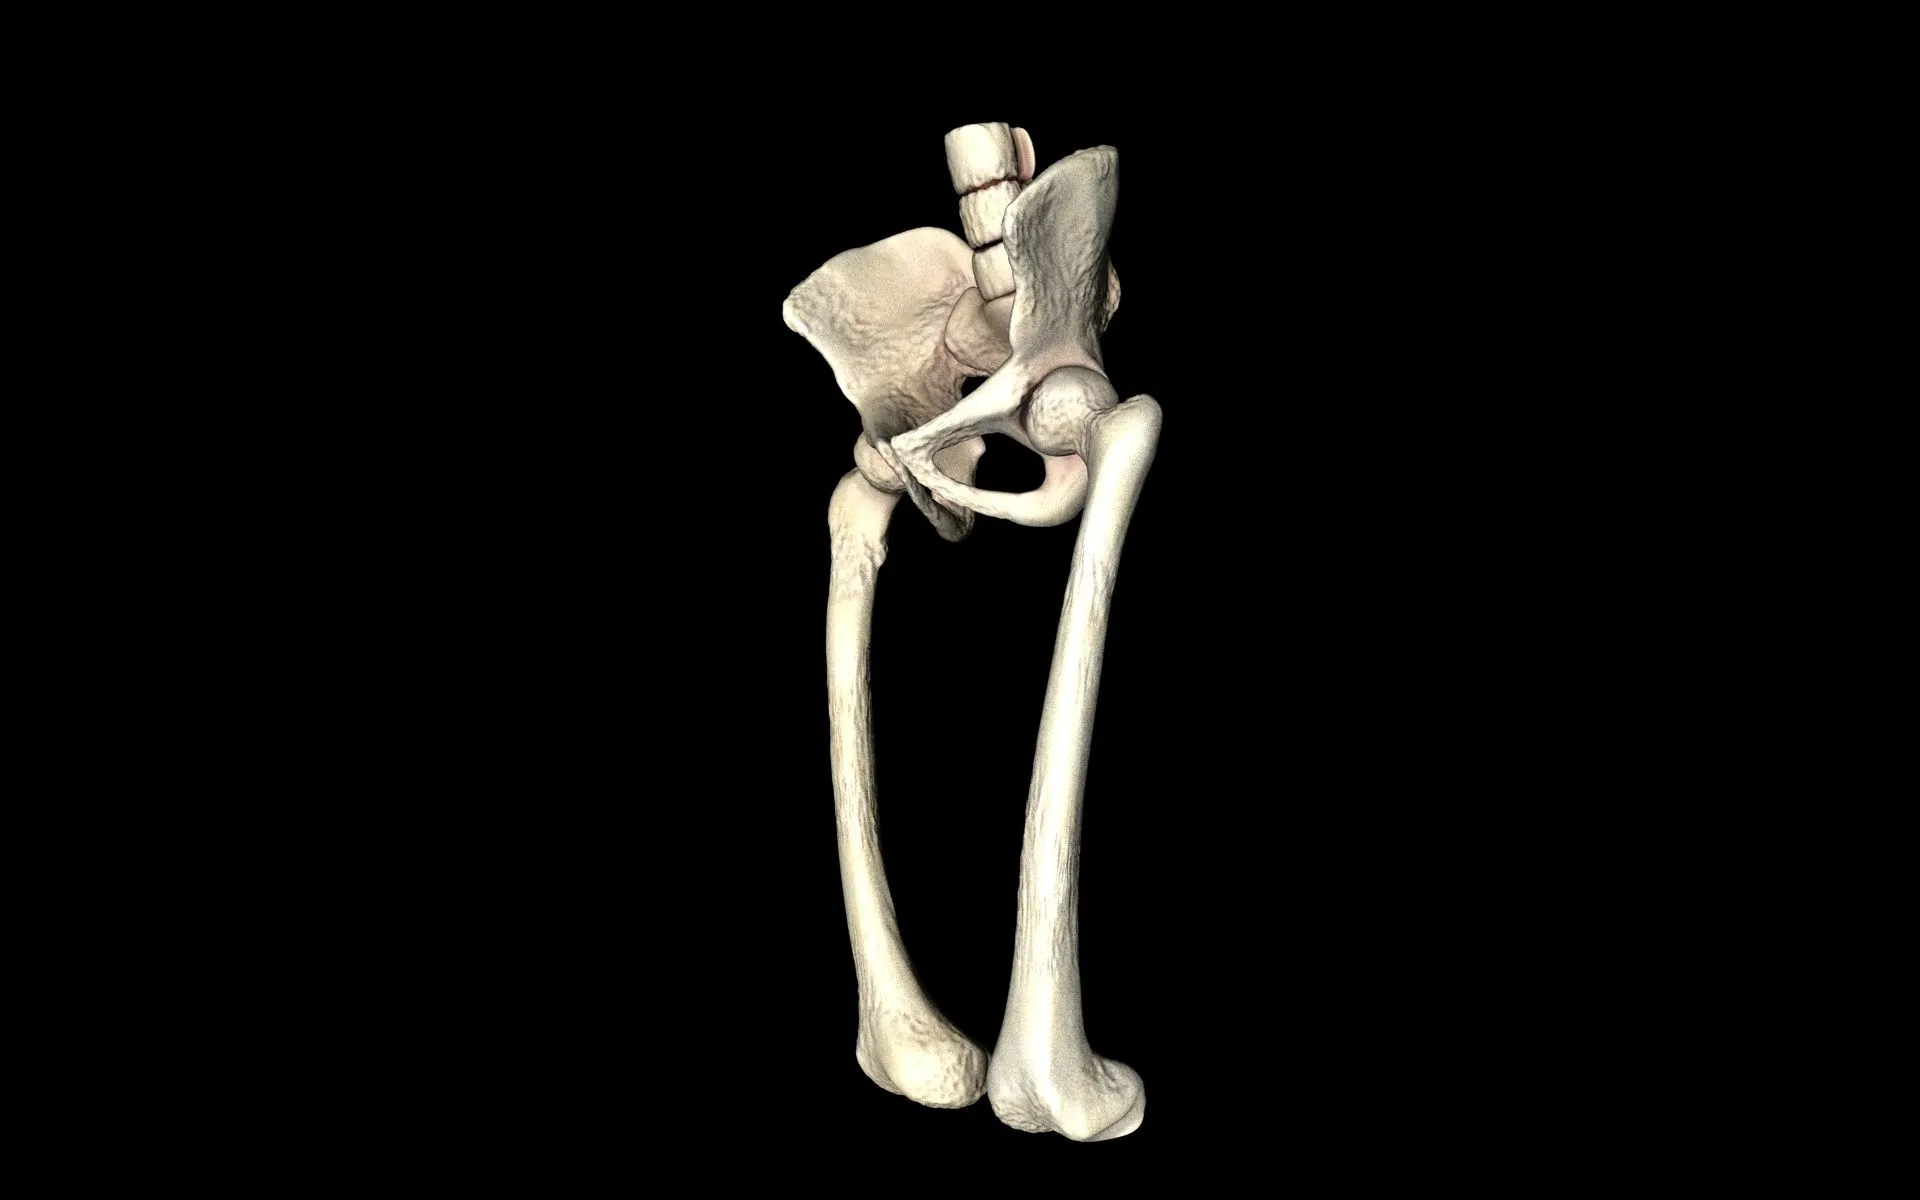

고관절은 골반의 관골구와 대퇴골두를 연결하는 관절입니다. 골반과 다리가 만나는 지점에 위치하며 체중을 지탱하고 다리의 움직임을 가능하게 합니다.

또한 "엉덩이 관절"이라고도 불리는 이 관절은 뼈와 뼈가 연결되어 자유로운 움직임을 가능하게 하는 신체 부위로, 허벅지와 종아리를 포함한 다리 전체를 움직일 수 있도록 돕습니다. 고관절의 움직임과 기능은 걷기, 달리기, 앉기 등과 밀접하게 연관되어 우리 몸의 움직임과 일상 활동에 핵심적인 역할을 수행합니다.